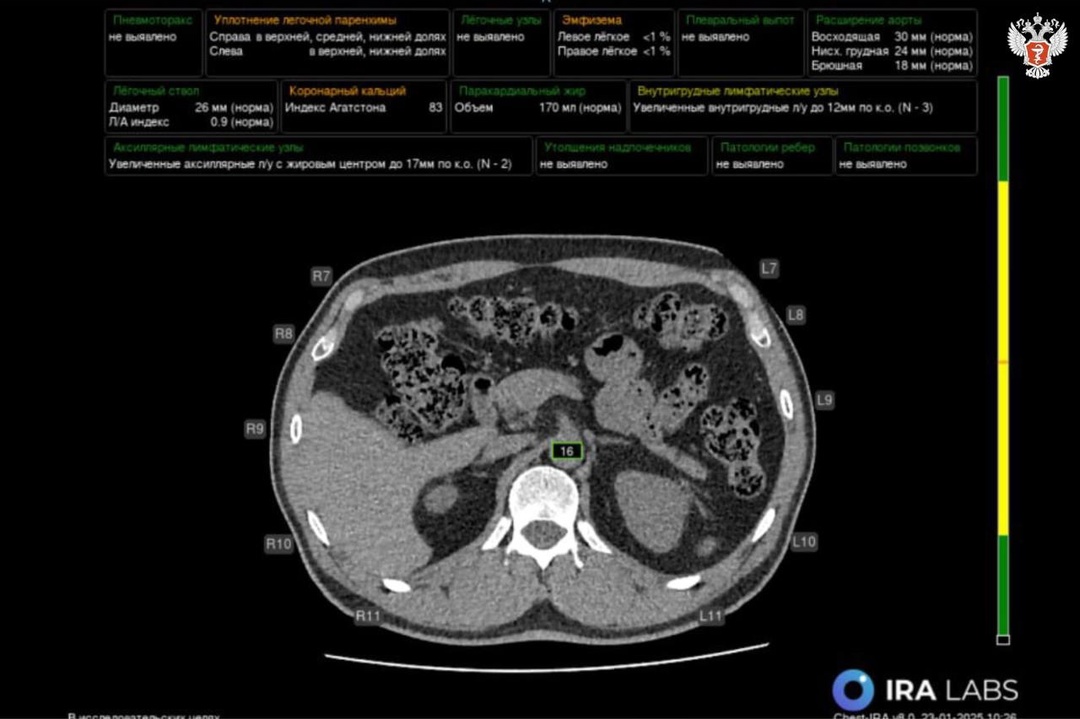

🖥 В медучреждениях Калмыкии внедряются сервисы с ИИ для расшифровки исследований

Искусственный интеллект анализирует любое исследование всего за 15 минут.

🩻 На сегодняшний день с использованием ИИ обработано более 7 тыс. исследований, патологии выявили в более 3 тыс. случаях.

Эти результаты свидетельствуют о высокой эффективности внедрения технологий в медицинскую практику, способствующих своевременному

обнаружению заболеваний и повышению точности диагностики.

🖥 Отметим, что в декабре 2024 года медучреждения Калмыкии подключилась к платформе, объединяющей 17 сервисов для анализа КТ, рентгенографии, маммографии и флюорографии.